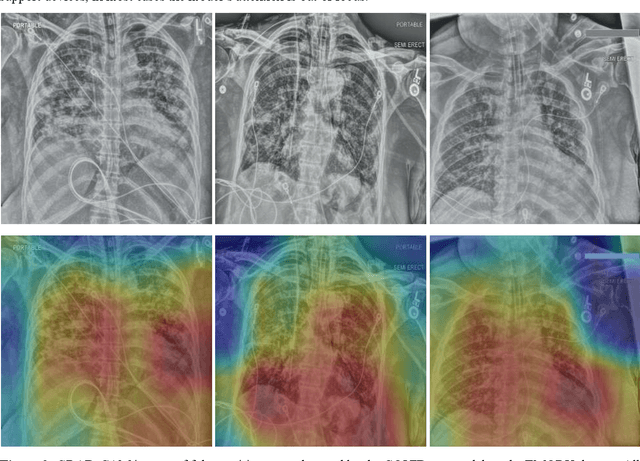

Abstract:Measures to predict 30-day readmission are considered an important quality factor for hospitals as accurate predictions can reduce the overall cost of care by identifying high risk patients before they are discharged. While recent deep learning-based studies have shown promising empirical results on readmission prediction, several limitations exist that may hinder widespread clinical utility, such as (a) only patients with certain conditions are considered, (b) existing approaches do not leverage data temporality, (c) individual admissions are assumed independent of each other, which is unrealistic, (d) prior studies are usually limited to single source of data and single center data. To address these limitations, we propose a multimodal, modality-agnostic spatiotemporal graph neural network (MM-STGNN) for prediction of 30-day all-cause hospital readmission that fuses multimodal in-patient longitudinal data. By training and evaluating our methods using longitudinal chest radiographs and electronic health records from two independent centers, we demonstrate that MM-STGNN achieves AUROC of 0.79 on both primary and external datasets. Furthermore, MM-STGNN significantly outperforms the current clinical reference standard, LACE+ score (AUROC=0.61), on the primary dataset. For subset populations of patients with heart and vascular disease, our model also outperforms baselines on predicting 30-day readmission (e.g., 3.7 point improvement in AUROC in patients with heart disease). Lastly, qualitative model interpretability analysis indicates that while patients' primary diagnoses were not explicitly used to train the model, node features crucial for model prediction directly reflect patients' primary diagnoses. Importantly, our MM-STGNN is agnostic to node feature modalities and could be utilized to integrate multimodal data for triaging patients in various downstream resource allocation tasks.